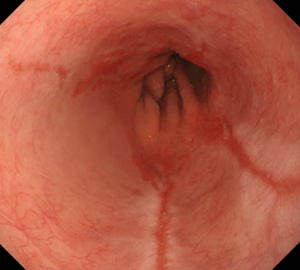

バレット食道オリンパス おなかの健康ドットコム。

好きです: 94